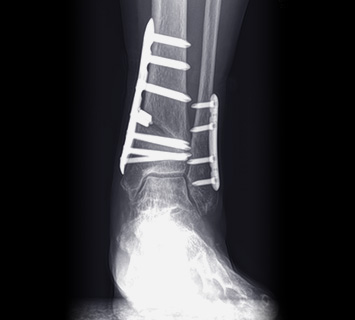

파열된 인대 주변에 뼈 조각이 없는 경우

관절경적 발목 인대 봉합 수술을 진행합니다.

3mm 초소형 관절경을 이용해 수술하므로

흉터와 조직손상도를 최소화하는 장점이 있습니다.

수술시간 약 30분. 1~2일, 길면 2~3일의 입원 기간 목표

통깁스3주 착용. 빠른 재활이 목표